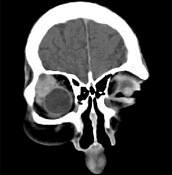

辅助检查中最有意义的发现是(如图)()

-